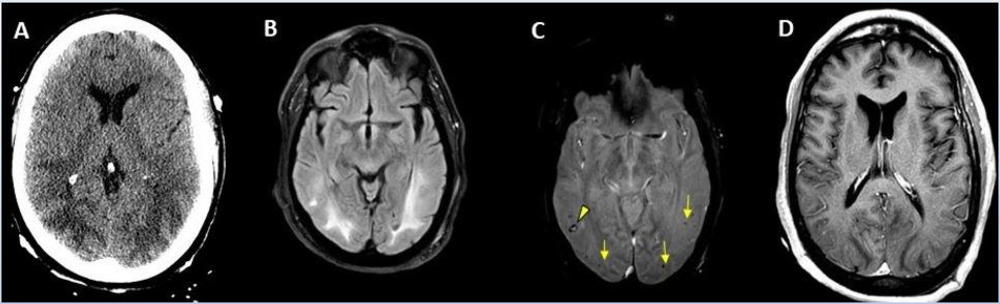

Figure 5. 56-year-old male patient with diabetes and hypertension who presented with complaints of confusion.

Figure 6. 49-year-old female with past medical history of mitral valve disease and tricuspid valve regurgitation who developed headache followed by cough and fever presented to the ER with right upper eyelid ptosis (drooping).